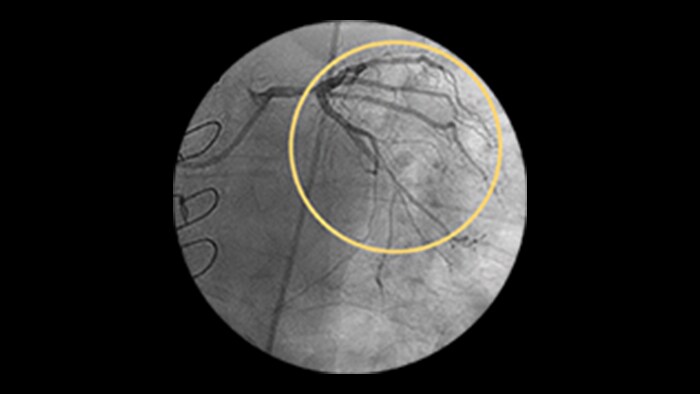

Dynamic Coronary Roadmap

This Philips-exclusive technology provides a real-time view of the coronary arteries and removes the need for additional contrast injections.